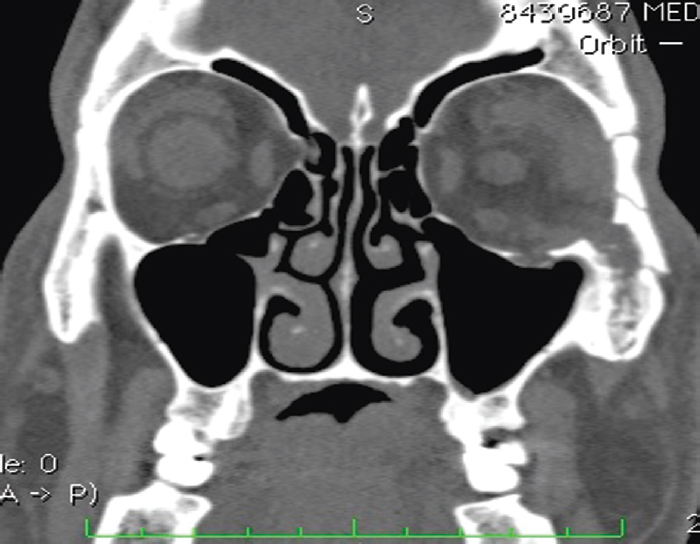

Fig. 6. Multispiral computed tomography. Frontal view. Two years after surgery. Titanium mesh over the zone of the defect. Spherical implant and external cosmetic prosthesis in the orbital cavity / Рис. 6. Мультиспиральная компьютерная томография. Фронтальный вид. Через 2 года после операции. Титановая сетка над зоной дефекта. В левой глазнице — сферичный имплантат и наружный косметический протез